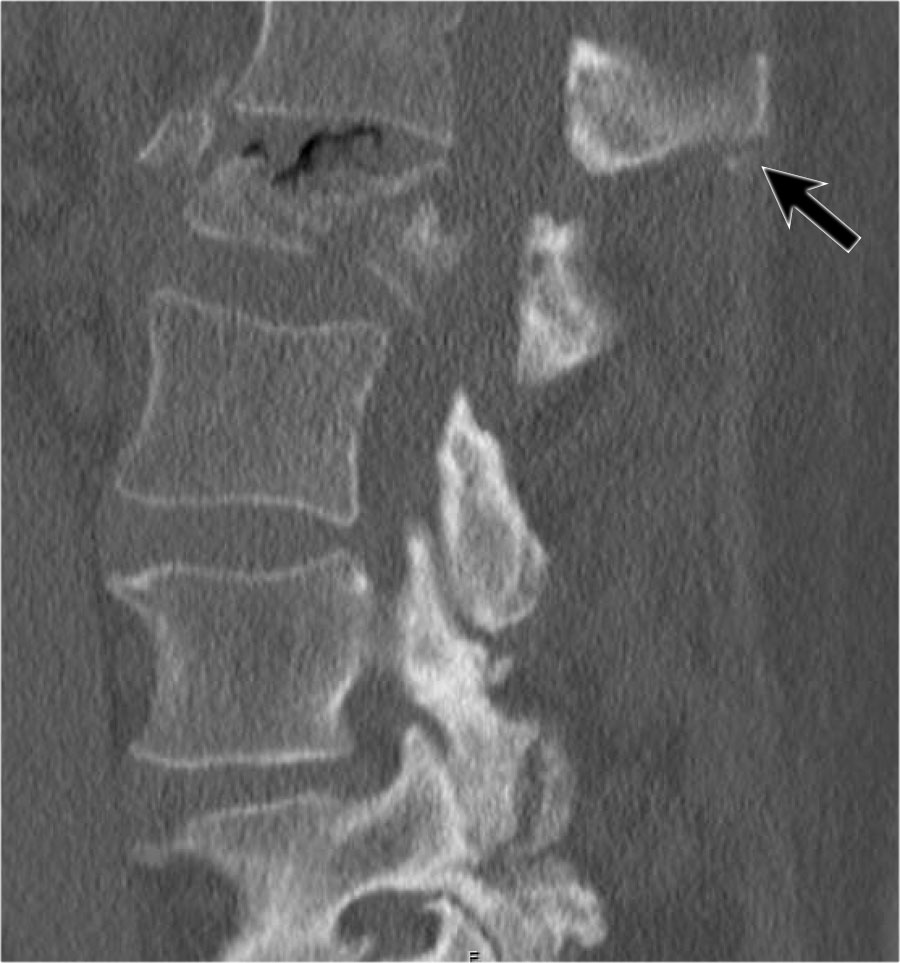

Hình ảnh cho thấy gãy đốt sống kèm gãy ngang mỏm gai, đồng thời có gãy xương ức.

Tuy nhiên, CT cho thấy một đường gãy mảnh qua mặt trước thân đốt sống và cả qua mỏm gai.